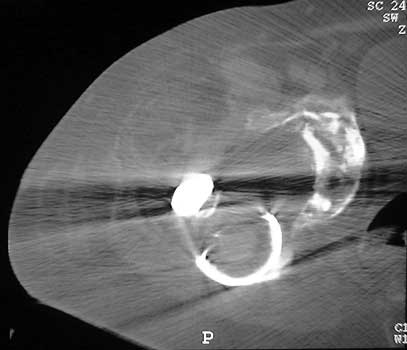

Dislocated femoral component and acetabular cup in grossly

loose arthroplasty. CT guided aspiration to rule out infection.